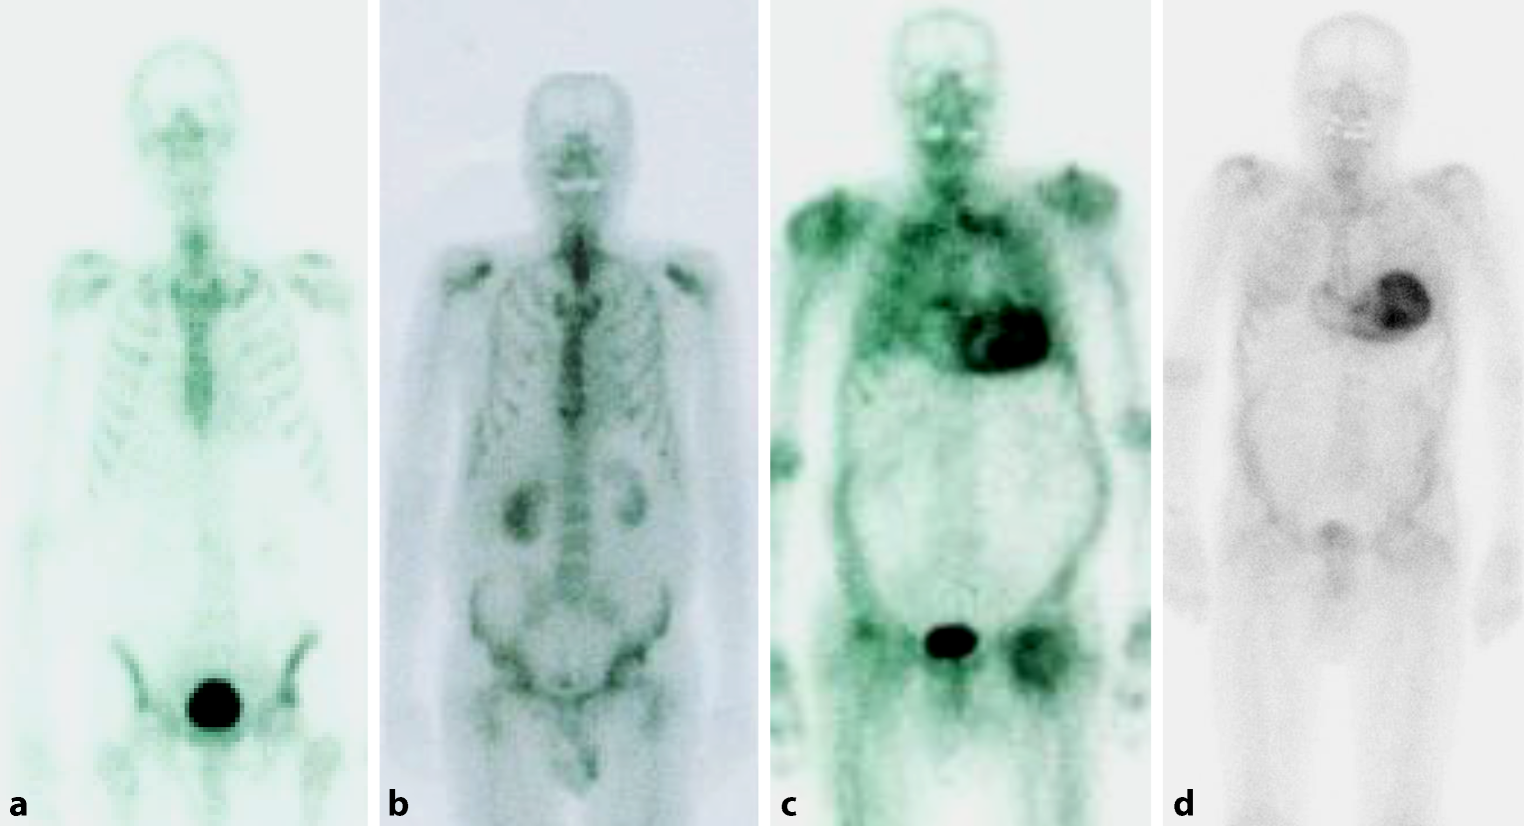

Perugini et al. suggested the following grading as the basis of assessment of the radionuclide uptake (Fig. 4; [89]):

• Grade 0: no cardiac uptake, regular osseous structures,

• Grade 1: minor cardiac uptake, with osseous structures appearing comparatively pale,

• Grade 2: moderate cardiac uptake, with osseous structures partly indistinct,

• Grade 3: strong cardiac update, markedly increased extracardiac retention in the soft tissue, with very indistinct osseous structures.

Fig. 4

Whole-body scintigraphy using 99mTc-labeled hydroxymethyl diphosphonate. a Healthy individual without any cardiac tracer uptake (Perugini grade 0). b Patient with cardiac light-chain amyloidosis (AL amyloidosis) and minor cardiac uptake (Perugini grade 1). c Patient with cardiac transthyretin amyloidosis (ATTR amyloidosis) and pronounced tracer uptake in the myocardium as well as attenuated osseous uptake (Perugini grade 2). d Patient with pronounced tracer uptake in the myocardium but only minor osseous uptake (Perugini grade 3)

Scintigraphy generally requires interpretation in the context of immunofixation/protein electrophoresis (see above), as pathological findings can also include patients with AL amyloidosis. Radionuclide accumulation does not necessarily correlate with the amyloid burden in biopsic material. [90] The sensitivity of DPD scintigraphy for diagnosis of cardiac ATTR amyloidosis in patients with strong tracer uptake (grade ≥2) has been reported to be up to 100% [31, 89, 91, 92]. In patients with distinct findings (grade ≥2, absence of monoclonal gammopathy), scintigraphy in combination with assessment of free light chains will confirm ATTR amyloidosis. In settings with unclear findings (e.g., grade 1), biopsy is inevitable.